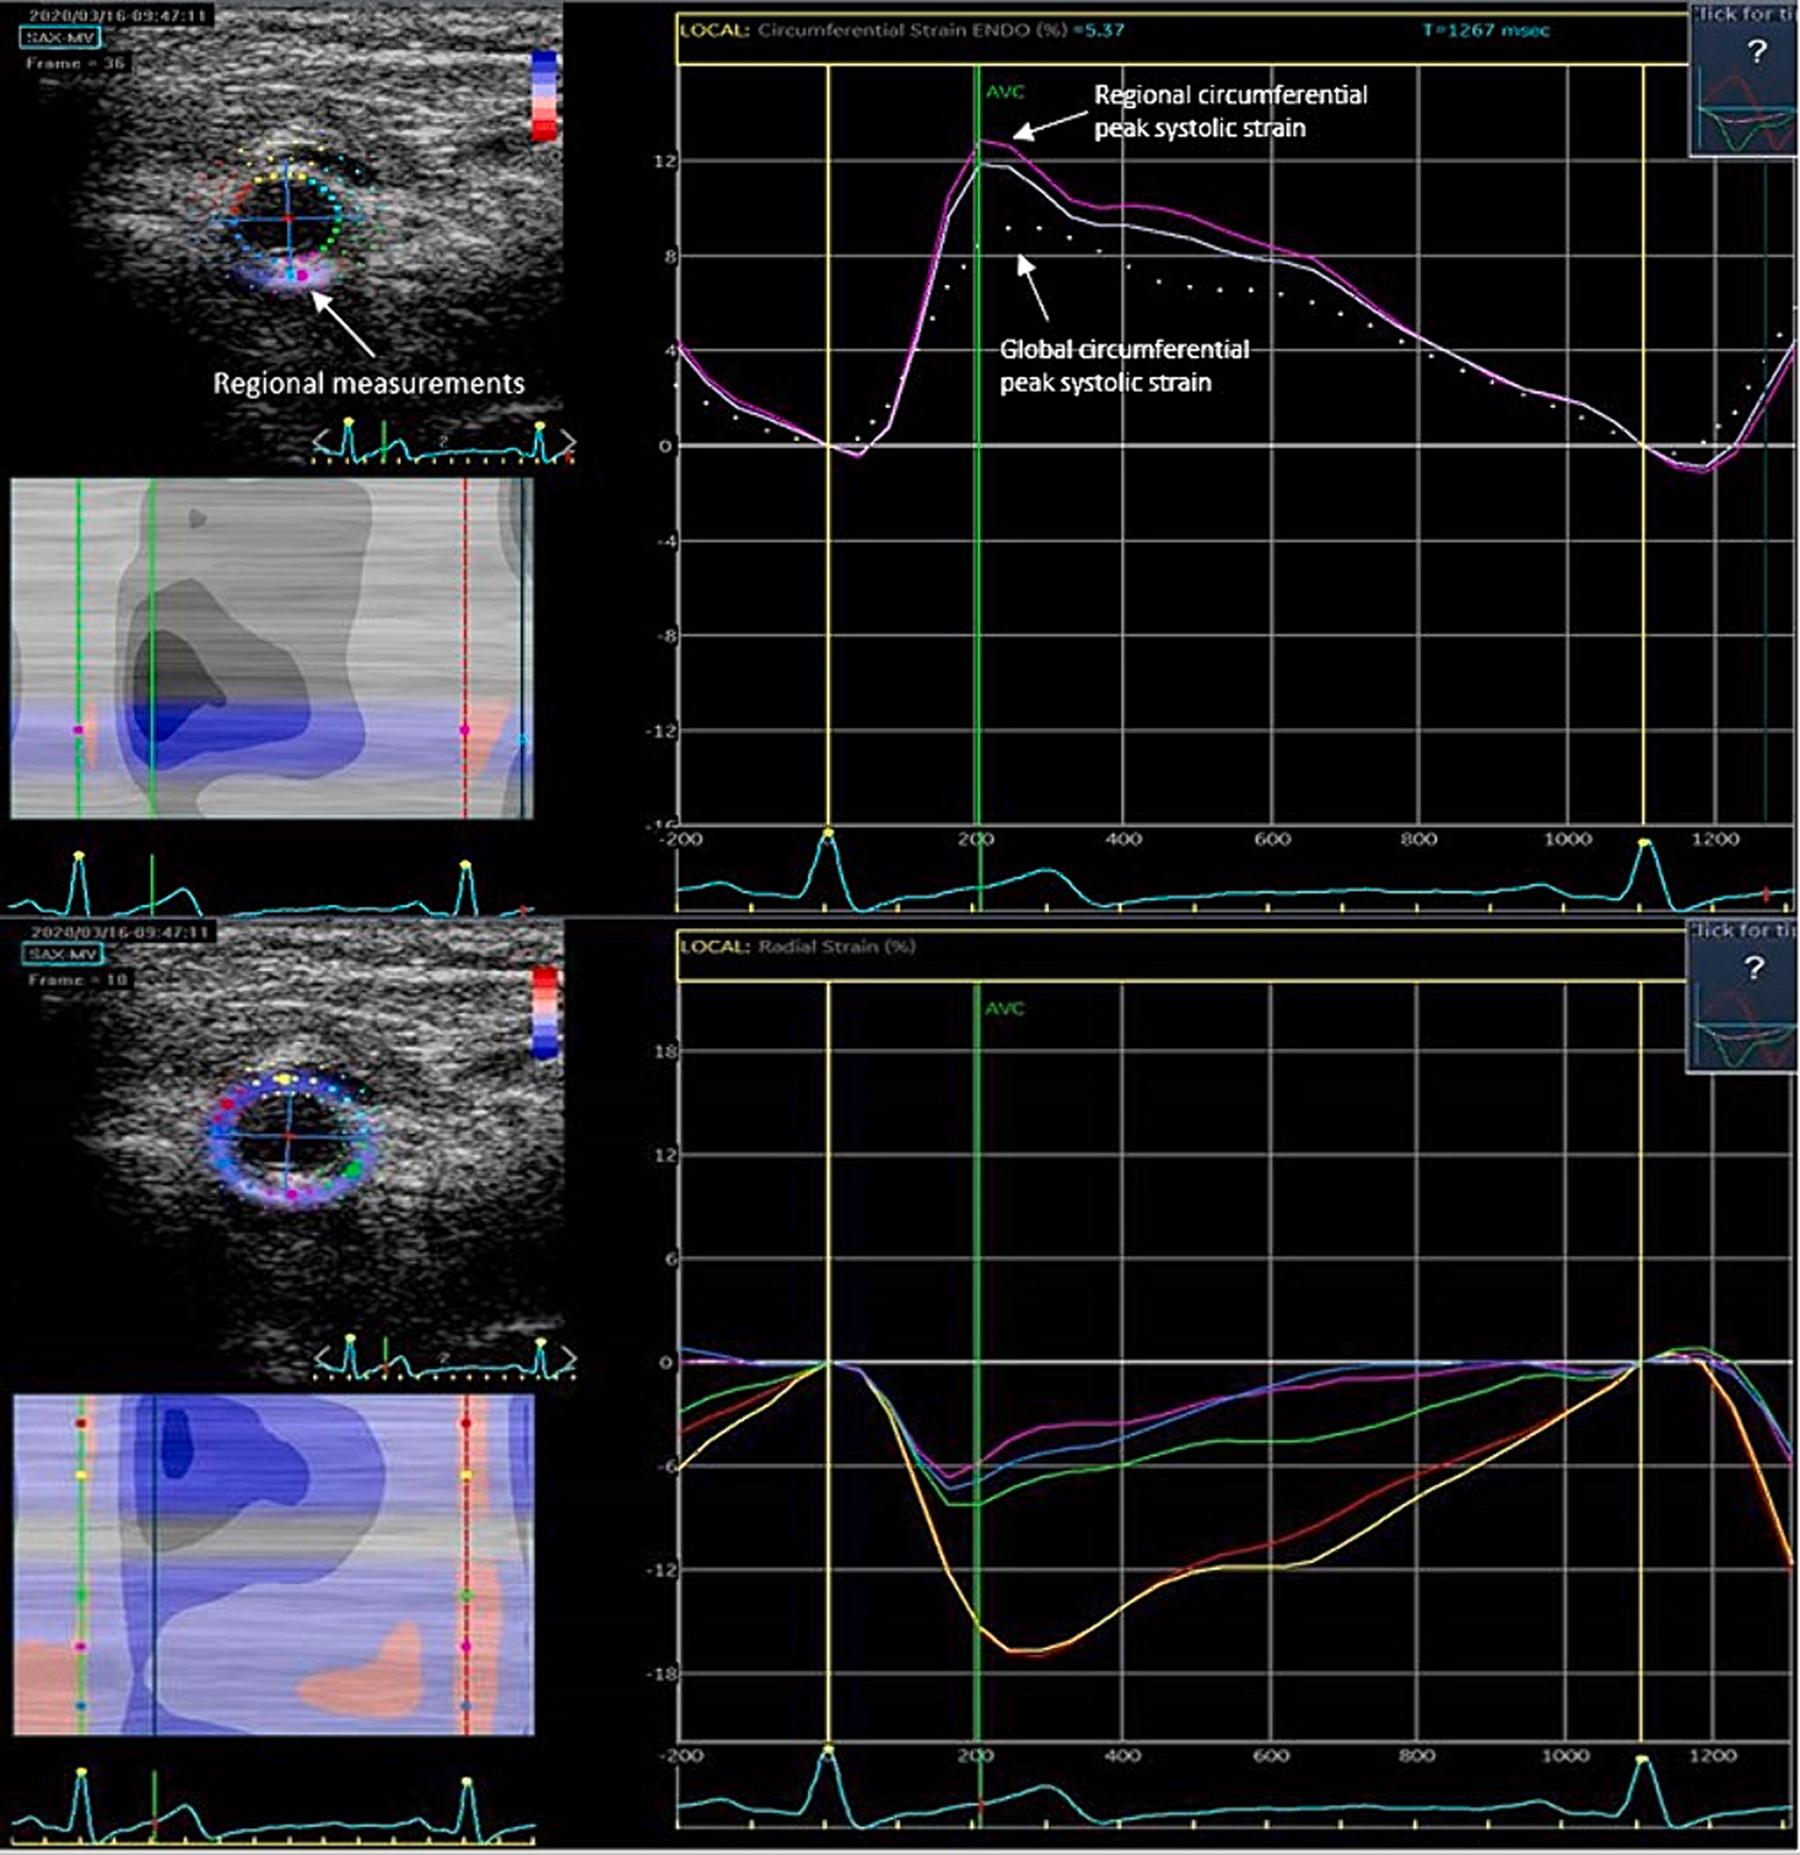

Bilateral carotid artery duplex studies were performed at 0, 3, 6, 12, 18 months and 2, 3, 4, and 5 years following RT. Intima media thickness (IMT); global and regional circumferential, as well as radial strain, arterial elasticity, stiffness, and distensibility were calculated.

在 RT 后 0、3、6、12、18 个月以及 2、3、4 和 5 年,对双侧颈动脉进行双功能超声检查。计算内膜中层厚度(IMT);计算全局和局部周向、径向应变、动脉弹性、僵硬和可扩张性。